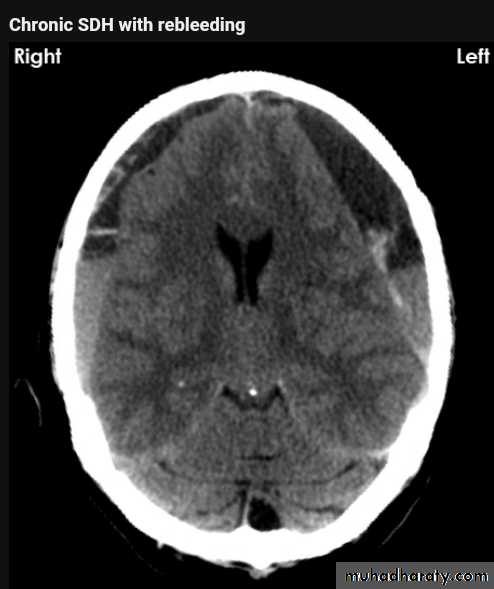

Acute SDH

CT findingCrescent shape or oval shape of hyper density area their inner medial margin is irregular shaggy

Associated with edema which cause shifting of the midline .

The source of bleeding hematoma is venous , not associated with # , but occur as a result of disruption of subdural vein , more commonly to occur in the old age group , due to brain concussion , ( brain atrophied wide SAS ) & in the pediatric age group the SAS &cistern are wide also .